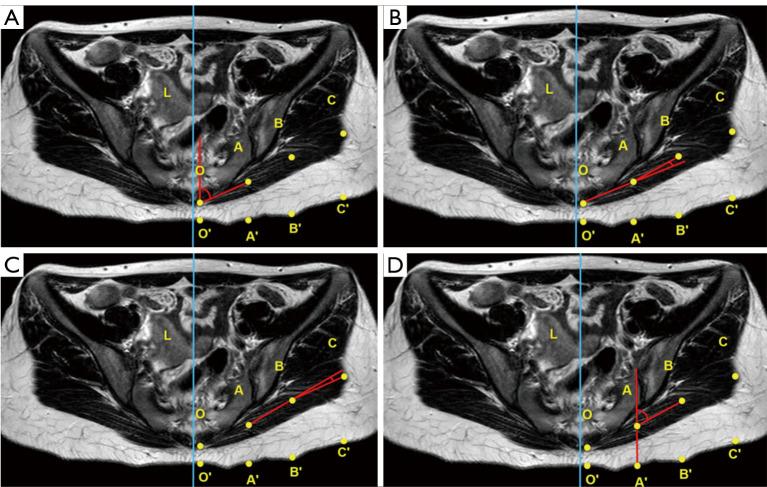

The objective of the current study was to retrospectively examine the morphological magnetic resonance imaging (MRI) characteristics of the gluteus maximus of buttock augmentation at levels of predetermined anatomic points.

The present study was a retrospective cross-sectional study. Adult women who underwent high-quality MRI scanning at Sun Yat-sen Memorial Hospital of Sun Yat-sen University from January 2018 to January 2021 were included in this work. The transverse MRI data measured at the inferior point of the sacroiliac joint, just above the femoral head, and at the ischial tuberosity were collected and statistically analyzed.

Fifty-two cases (104 sides of female gluteus maximus) were included in the final analysis. The A point (surgery starting point) were 54.4±6.34 mm, 54.91±5.57 mm, and 73.91±5.57 mm away from the posterior midline at the level of inferior point of the sacroiliac joint, just above the femoral head, and at the ischial tuberosity, respectively. Accordingly, the thickness of the muscle at these locations was 16.0±4.17 mm, 23.4±4.40 mm, and 24.6±7.58 mm, respectively. The diameter of the implant did not exceed 14.18±1.22 cm. In addition, the gluteus maximus at the lowest point of the sacroiliac joint and above the femoral head exhibited an arc structure, which needs to be tilted to the deep plane during separation.

本研究的目的是回顾性地研究在预定解剖点水平下用于臀部增大的臀大肌的形态磁共振成像(MRI)特征。

本研究为回顾性横断面研究。纳入了2018年1月至2021年1月在中山大学孙逸仙纪念医院接受高质量MRI扫描的成年女性。收集在骶髂关节下点、股骨头上方和坐骨结节处测量的横向MRI数据并进行统计分析。

最终分析纳入了52例(104侧女性臀大肌)。A点(手术起始点)在骶髂关节下点、股骨头上方和坐骨结节水平分别距离后正中线54.4±6.34mm、54.91±5.57mm和73.91±5.57mm。相应地,这些位置的肌肉厚度分别为16.0±4.17mm、23.4±4.40mm和24.6±7.58mm。植入物直径不超过14.18±1.22cm。此外,骶髂关节最低点和股骨头上方的臀大肌呈弧形结构,分离时需要向深层平面倾斜。